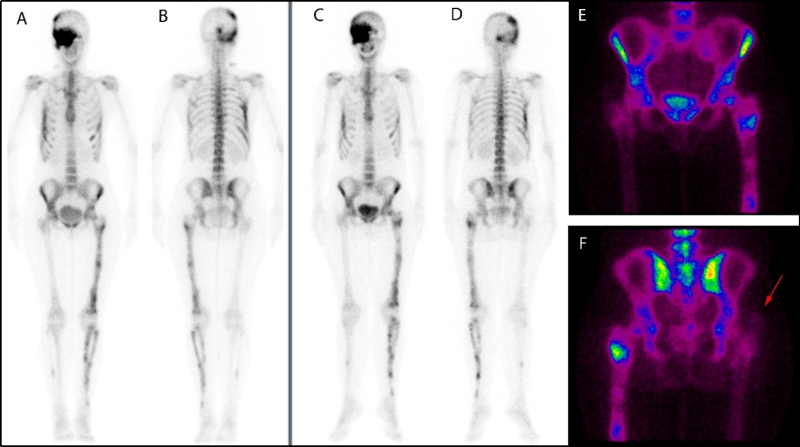

Paciente mujer de 37 años diagnosticada previamente de displasia fibrosa mediante gammagrafía ósea con 99mTc-HMDP realizada en 2015, que mostró un aumento de la captación hemicraneal derecha (involucrando regiones parietal, temporal, occipital y huesos del macizo facial), arcos costales (5º, 6º, 7º, 10º derechos y 6º izquierdo), miembro inferior izquierdo (fémur, tibia y peroné) y peroné derecho. Las lesiones eran sugestivas de displasia fibrosa poliostótica que fue posteriormente verificada mediante biopsia ósea realizada en la zona distal del fémur izquierdo y en el décimo arco costal posterior derecho (fig. 1, A y B). Durante la realización de una nueva gammagrafía ósea de seguimiento en 2021, la paciente refirió masa palpable en región glútea derecha de varios meses de evolución. La gammagrafía no mostró cambios significativos en la captación ósea relacionada con su displasia fibrosa ya conocida (fig. 1 C y D); sin embargo, se observó captación patológica en partes blandas de la región glútea derecha. Dada la clínica dolorosa en esa localización, se recomendó realizar una técnica de imagen morfológica para valorar mejor este hallazgo (fig. 1 E y F).

La resonancia magnética (RM) de cadera demostró una lesión ovalada localizada en el músculo glúteo mayor derecho en su región más superficial y externa, de 3,3 x 2,6 x 3,9 cm (fig. 2, flechas rojas). La secuencia T1 (A) mostró lesión hipointensa, con el anillo graso característico de los mixomas alrededor de la lesión. En la secuencia T2 (B) la lesión fue hiperintensa, y en la secuencia T2 (C) con supresión grasa la lesión fue también hiperintensa. Después de la administración de gadolinio, se demostró realce difuso (D). En el fémur izquierdo se observó una lesión endomedular bien definida con borde esclerótico, compatible con la displasia fibrosa conocida. Se realizó biopsia con aguja gruesa guiada por ultrasonido de la masa glútea; el resultado fue compatible con mixoma.